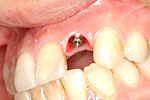

症例 15

① 治療前、左下奥歯がありません。

② インプラント手術後土台を立てたところです。

③ 固定式のセラミックの歯が入りました。

50才代 女性

総額:89万円(税別)

治療期間:4ヵ月

リスク副作用:噛み合わせに負担がかかりすぎるとセラミックが破損することがあります。